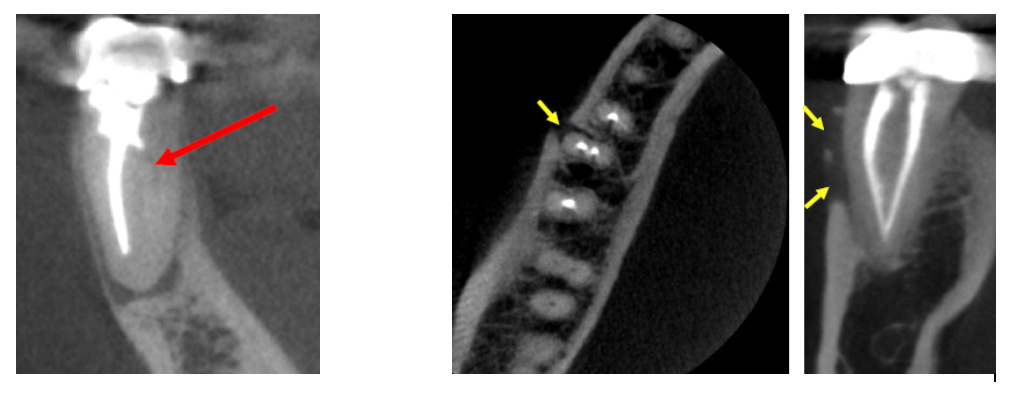

Cone beam computed tomography (CBCT) offers accurate and high quality 3-D representations of dental and facial structures. This enables our endodontists to more precisely diagnose an underlying problem, detect unforeseen defects, and minimize the need for exploratory procedures. CBCT facilitates more effective care and more consistent successful outcomes.

Clinical applications of CBCT technology in endodontics include the following:

Occasionally, dental defects or pathology that deem a tooth non-restorable will be revealed on a CBCT scan. If this happens, the endodontist will advise you that the tooth cannot be saved.

(Pictures of missed canal, vertical root fracture, extra tooth, and resorption)